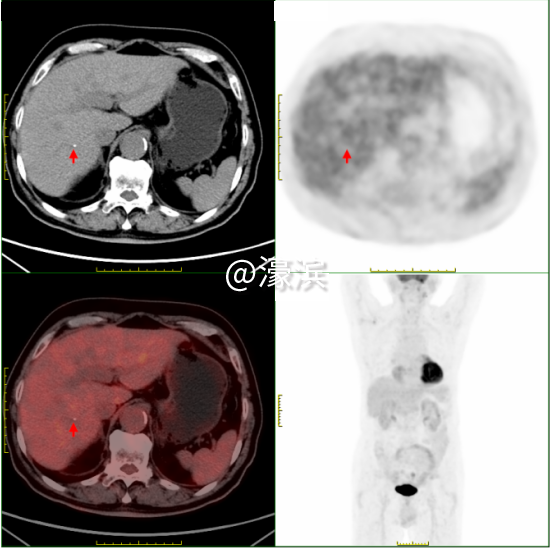

·0.2cm肝钙化灶(小于普通CT最小分辨单位)  ·0.6cm肾结石(超声检查受肠气干扰易遗漏) 精准诊断:全身隐匿病灶"无处遁形"

①食管癌精准定位 发现食管下段1.3cm管壁增厚伴FDG代谢增高(SUVmax 3.1),与病理结果高度吻合,为后续手术或放疗提供精准靶区定位。 ②全身隐匿病灶"无处遁形" 鉴别颈部炎性淋巴结(SUVmax 4.2)与转移灶,避免过度治疗;发现双肾囊肿(最大3.6cm)、肝囊肿等良性病变,完善全身健康评估;识别牙槽根周炎症(SUVmax 10.9)、上颌窦炎等感染灶,指导抗炎治疗。 ③全身健康"全景扫描" 同步检出肺气肿、冠脉钙化、前列腺增生伴钙化等退行性病变,精准锁定多处微小病灶,为多学科诊疗提供完整数据支持。 "对于SUVmax<2.5的病灶,如本例患者的食管癌灶,我们也能通过双能谱CT物质分离技术,识别早期癌变的特征性脂质成分变化。"瑞慈医院医学影像科核医学组主任夏淦林提到,"PET-CT不是简单的影像设备,而是现代精准医疗的决策中枢,精准捕捉到<1cm的微小病灶。" 选择瑞慈PET-CT的四大理由?  (一)美国GE进口超高清设备:高灵敏度、高清晰度、高分辨率、高扫描速度、高精准定量测量 (二)专业影像科团队:从业20余年的“南通PET-CT第一人”领衔解读诊断报告 (三)检查快速高效:提前一天预约即可检查,检查后最早当天下午出报告,最晚第二天上午出报告。 (四)星级检查环境:独立贵宾休息室,隐私零干扰、全流程单向通行,动线设计更科学。 PET-CT主要解决哪些问题? PET-CT在肿瘤方面的应用占其床应用的90%以上。 主要适应症如下: 协助诊断 ·对肿瘤高危人群,早期发现或排除肿瘤; ·对肿瘤标志物高或副肿瘤综合征患者,寻找肿瘤病灶所在; ·对已发现可疑病变者,鉴别良、恶性; ·对可疑肿痛患者,指导选择活检部位; ·对已发现肿瘤转移者,寻找原发灶。 指导治疗 ·对恶性肿瘤患者,进行更准确分期,全面了解全身病变情况; ·肿瘤恶性程度分级和预后判断; ·指导放疗计划靶区的设定。 疗效评估和复发监测 ·肿瘤治疗效果的评估; ·肿瘤残存病灶与坏死、纤维化组织的鉴别; ·肿瘤治疗后标志物仍高或重新升高,寻找残存、复发或转移病灶; ·肿瘤复发的监测。